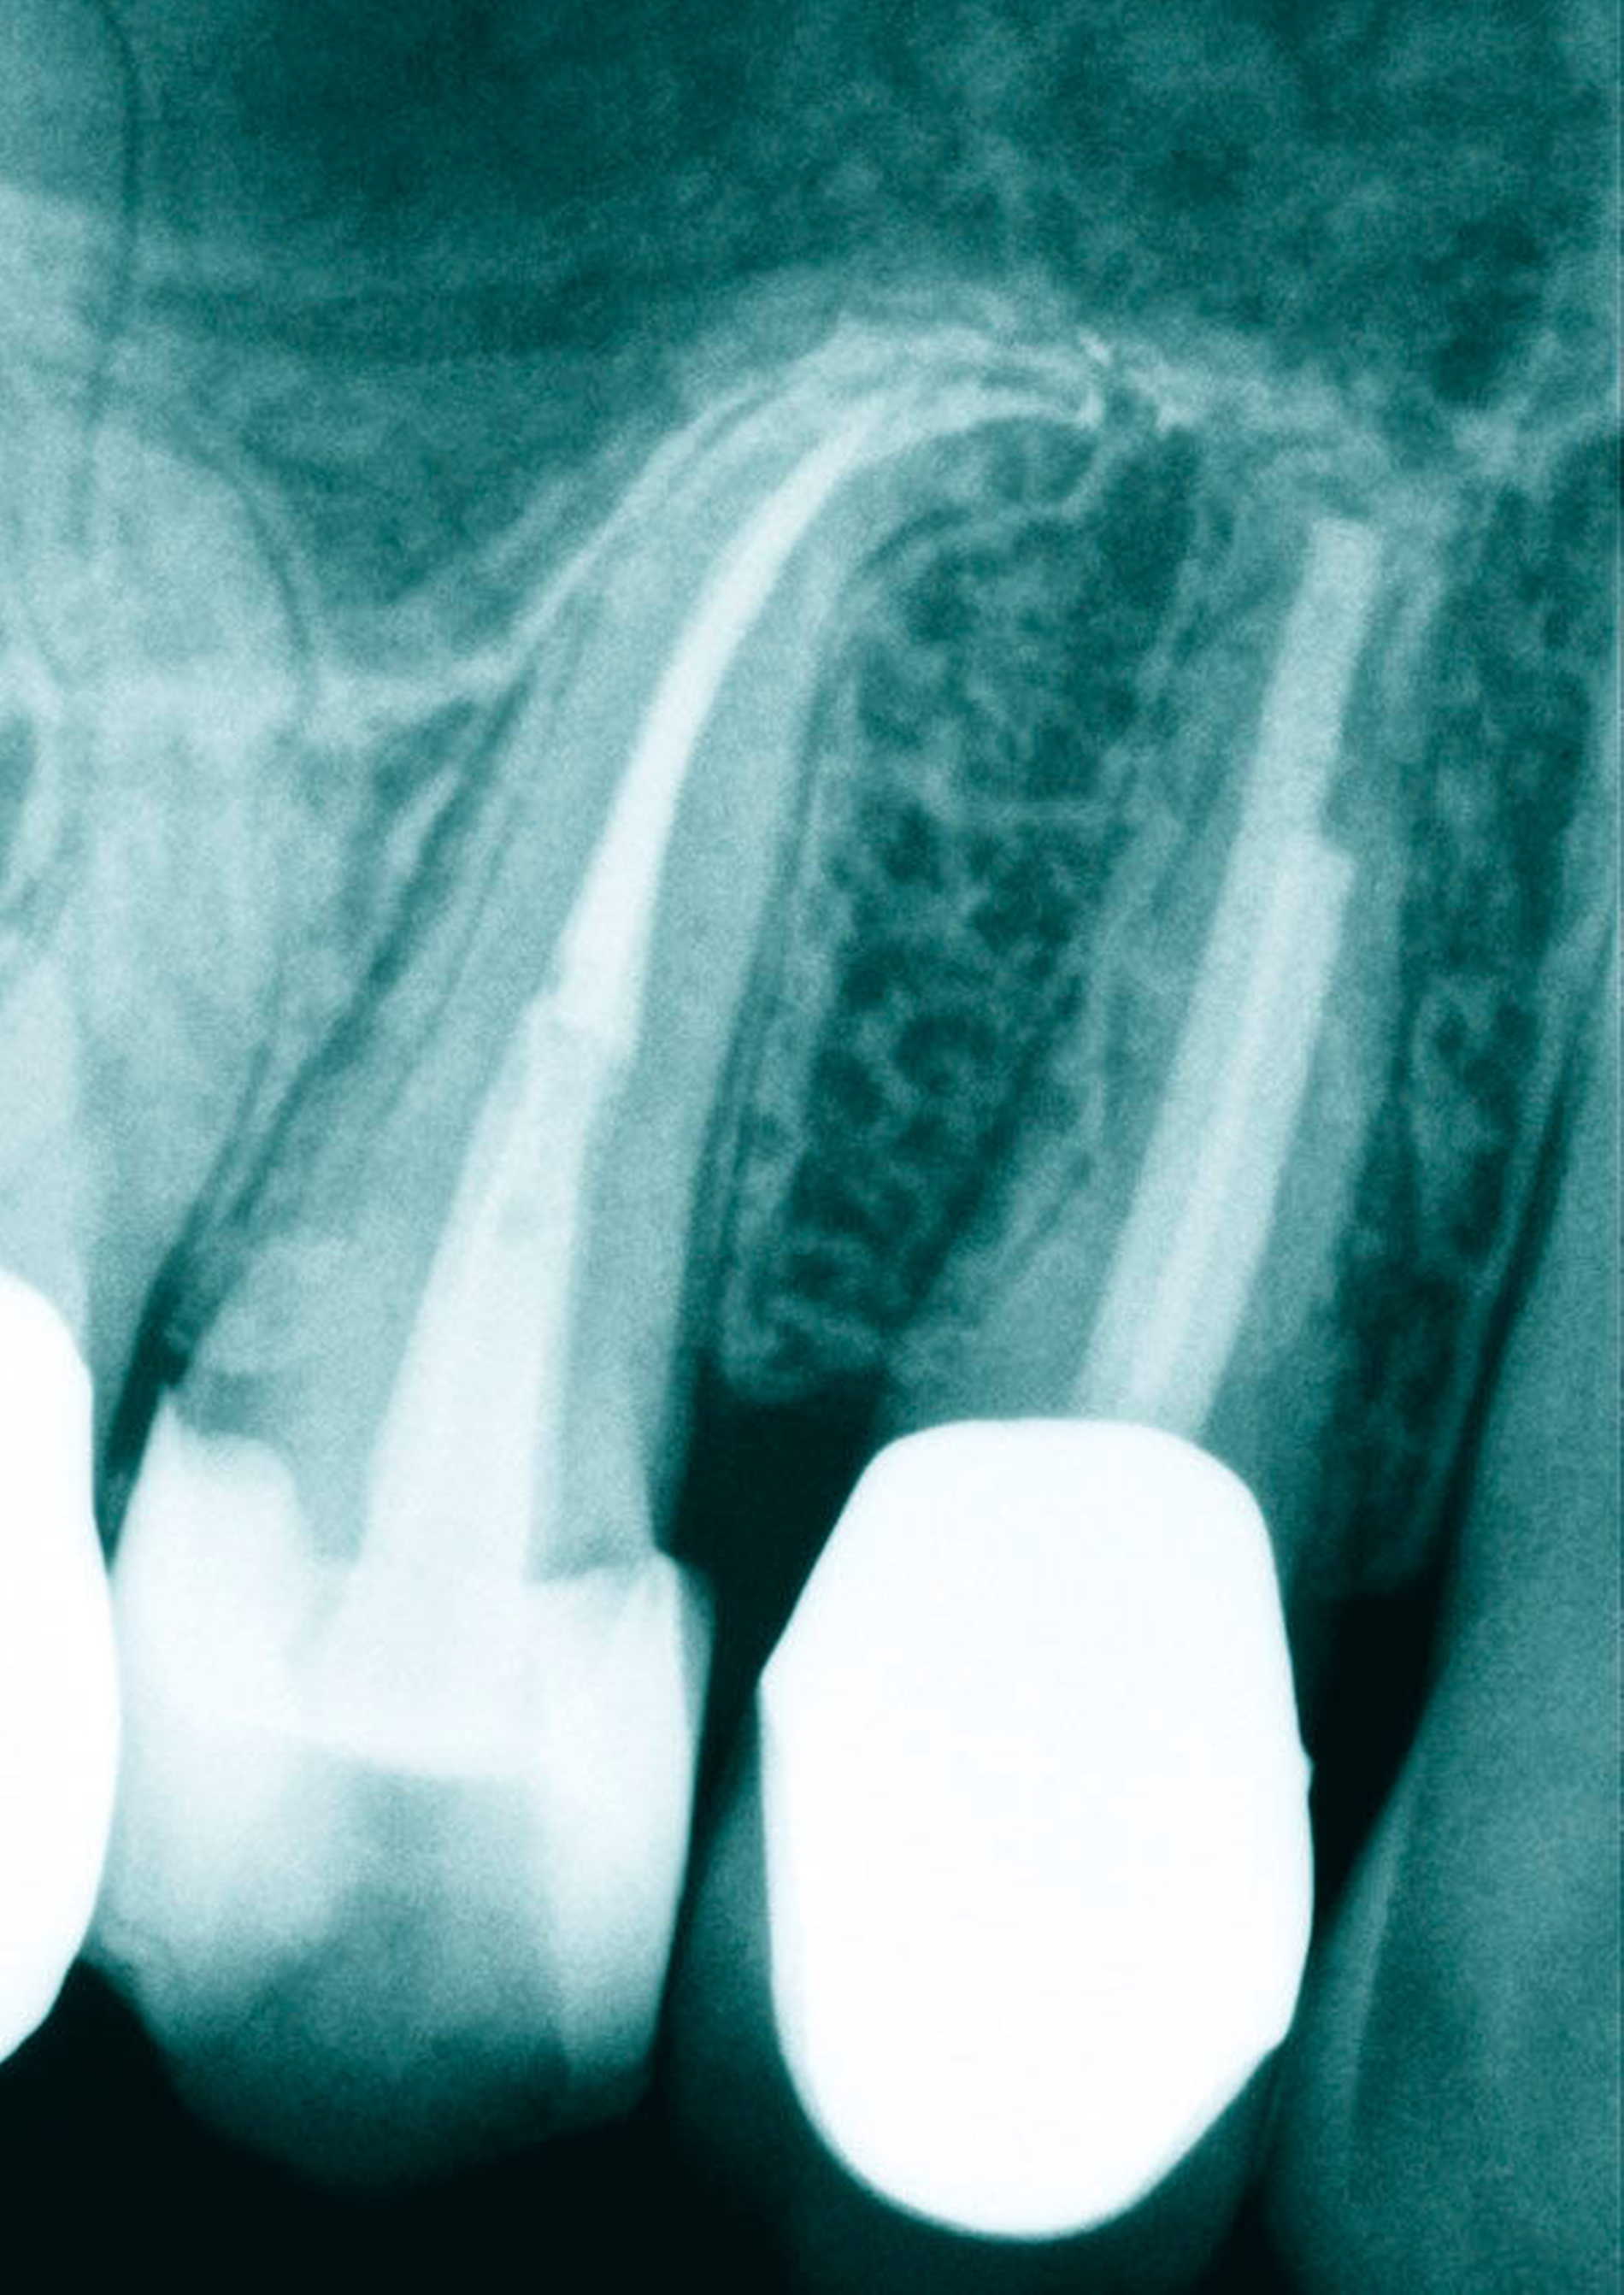

Die Krümmungen folgen bei beiden Zähnen in der Regel dem distalen Krümmungsmerkmal. Eine starke Ausdehnung der Kieferhöhle scheint jedoch für starke apikale Krümmungen der Wurzeln nach mesial oder distal verantwortlich zu sein. Ebenfalls nicht selten anzutreffen sind Doppelkrümmungen der Wurzeln (Abbildung 3).